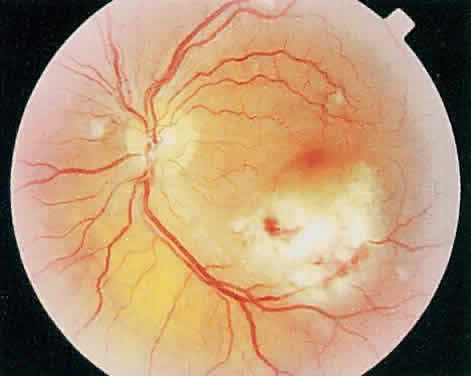

Over a course that usually spans weeks, infiltrates of CMV tend to assume two different patterns of clinical disease.11,12 The first pattern is called hemorrhagic and is characterized by broad geographic zones of retinal whitening. These large, geographic lesions are usually in close proximity to a major retinal blood vessel or the optic nerve. Satellite lesions are common. When the retinal necrosis associated with CMV retinitis becomes widespread, it is almost invariably associated with retinal hemorrhages. Although the border between necrotic and unaffected retina is sharply demarcated, the border itself appears irregular and jagged. Exudation into the retina or subretinal space may be seen, adding to the granular appearance of the retinitis. Juxtaposition of large zones of white, granular necrosis with those of red retinal hemorrhage has led this appearance of CMV retinitis to be described as either “pizza-pie” or “cheese and ketchup.” The retinal blood vessels, both arteries and veins, in the areas of necrosis commonly appear sheathed, secondary to a vasculitis. As a consequence, secondary retinal vascular occlusions, especially branch retinal vein obstructions, may occur in the course of CMV retinitis. Immune-mediated vascular damage may play a role in the vasculitis.12 Central healing of these lesions will occur as the infection progresses. Avasculitis resembling “frosted branch angiitis” hasbeen reported (Fig. 2).28 A second pattern of CMVretinitis has been labeled “granular” or “brushfireborder.” In this appearance, the focal granular infiltrates enlarge slowly across a line, leaving ever-increasing areas of destroyed retina and atrophic retinal pigment epithelium behind. Hemorrhages and vitreous cells are a less prominent feature. There appears to be direct cell-to-cell transfer of infected virions in this pattern of infection (Figs. 3 and 4). The brushfire border is commonly seen in CMV retinitis lesions anterior to the equator (Fig. 5). The significance, if any, of these two clinical patterns of CMV retinitis is not known, and, in some eyes, both patterns of disease can be seen simultaneously or in sequence. Progression of retinitis has been defined in clinical trials as movement of a lesion border at least 750 μm along a front that is 750 μm or more in length, development of a new CMV lesion in a previously involved eye or in the uninvolved fellow eye of a patient with baseline unilateral disease.29 Without treatment or improvement in the host's immune system, CMV retinitis is a relentless, slowly progressive infection resulting in blindness caused by total retinal necrosis, retinal detachment, or optic nerve involvement, in any combination.

Fig. 2. Active cytomegalovirus retinitis concentrated around the optic nerve. Temporal to the fovea, there is perivascular whitening with a frosted branch angiitis appearance.